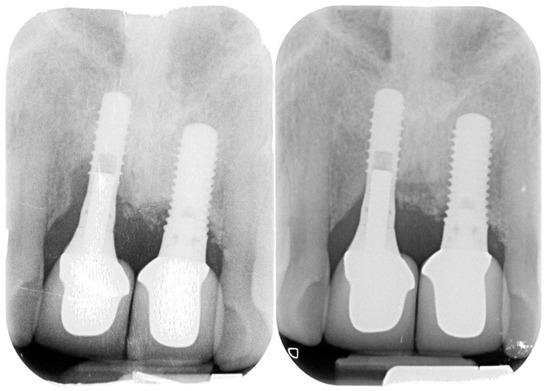

Peri-Implantitis: Application of a Protocol for the Regeneration of Deep Osseous Defects. A Retrospective Case Series

2. Materials and Methods

3. Results